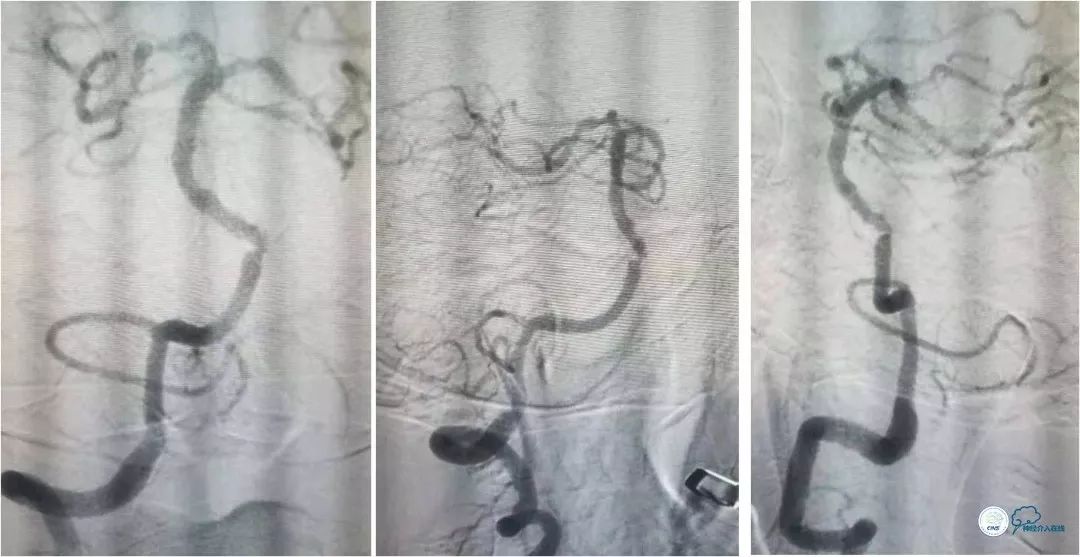

DSA提示:左椎动脉开口迂曲,右椎动脉开口中度狭窄(图5)。双椎动脉V4段与基底动脉交界处重度狭窄,左侧狭窄程度更重(图6,7)。

全麻下右侧股动脉穿刺置入6F动脉鞘, 6F导引导管至左椎动脉V2段远端,术前造影示左椎动脉V4段与基底动脉交界处重度狭窄(图8)。

路径图下经交换技术送入Transend微导丝(0.014″,300cm)至左大脑后动脉。沿微导丝送入Gateway球囊(2.25mm×9mm)于狭窄处预扩张,扩张后造影提示狭窄程度明显改善(图9)。

撤出球囊导管,送入wingspan (2.5mm x 15mm )自膨式支架,造影提示支架释放后支架贴壁良好,前向血流TICI 3级。右椎动脉V4段经返流显影,但病变受支架影响显示狭窄程度加重(图10)。